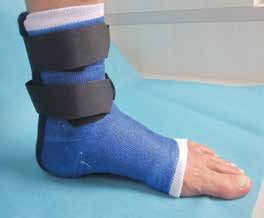

Dem Patienten wurde eine orthopädische Innenschuhorthese als Versorgung vorgeschlagen (Abb. 2). Um diese zu testen, wurde dem Patienten ein abnehmbares Soft-Cast-Stiefelchen (Abb. 3 und 4) mitgegeben. Dieses konnte sofort angefertigt werden und zeigte unmittelbar den gewünschten Erfolg, sodass die vorgeschlagene Versorgung nach kurzer Zeit ausgeführt werden konnte (Abb. 5).